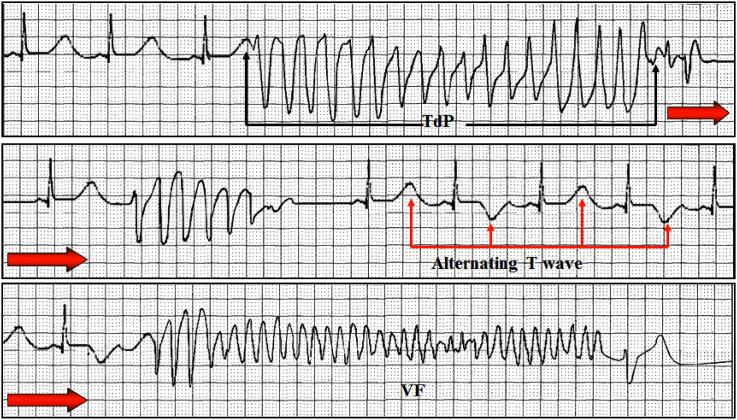

先天性长QT综合征3型(LQT3)在目前已知的15种先天性长QT综合征(LQTS)中,发病率位列第三。与LQT1和LQT2相比,LQT3中心脏事件的发生频率较低,但更有可能致命;在发生心脏事件时,LQT3突变家族的死亡概率为20%,而LQT1或LQT2突变家族为4%。LQT3是由编码Nav1.5钠通道α亚基的SCN5A基因突变引起的,其心电图特征为与年龄相关的心动过缓倾向、QT/QTc间期延长(平均QTc值478±52毫秒)、ST段延长导致QT离散度增加、T波出现较晚以及由于左心室壁M细胞复极化时间延长而频繁出现明显的U波。